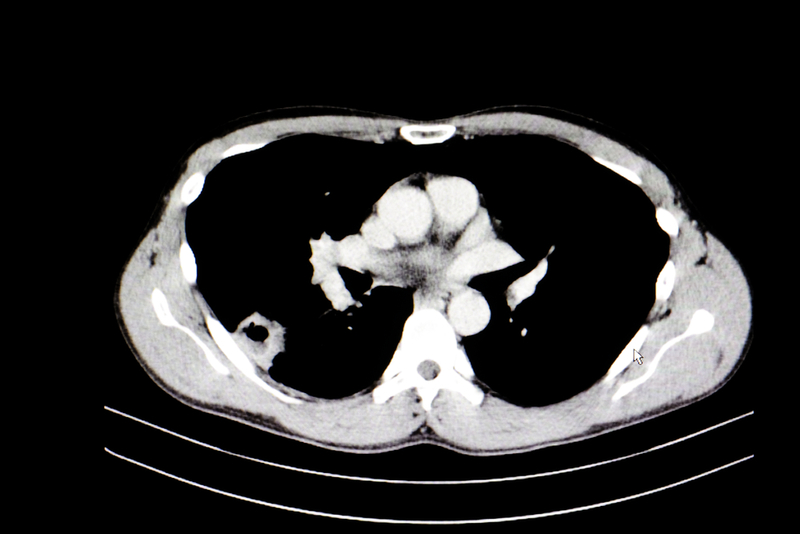

When the patient, a 33-year-old woman, visited the hospital she had a 5-day history of fever and cough of unknown cause. The brief paper explains her clinical conditions. Based on the epidemiological characteristics, clinical manifestations, chest images, and laboratory findings, her physicians made a diagnosis of 2019-nCoV pneumonia. After receiving 3 days of treatment, combined with interferon inhalation, she was clinically worse.

Image used is for illustrative purposes only and does not represent a true or accurate depiction of the news report.